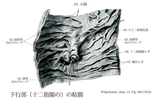

十二指腸【じゅうにしちょう】 The ca. 25-30 cm long segment of the small intestine between the pylorus and duodenojejunal flexure.(十二指腸は胃の幽門から十二指腸空腸曲まで約25cmの腸管。十二指腸Duodenumは12で、intestinum duodenum digitorumの意味。長さが指を12本横にならべた幅に等しいことによる。第1腰椎の椎体右縁の前方ではじまり、C字状に屈曲して膵臓の頭を取り囲む。腸間膜を欠き、後腹膜臓器の一つであり、胆管、膵管が開口するなど他の小腸とは異なる。十二指腸には4部が区別される。上部は幽門につづく5cmの長さの部で、上背外側へはしる。最初の2.5cmは可動性。上縁には小綱が付着する。上十二指腸曲において、ほぼ下方へ屈曲し、下行部(約8cm)へ移行する。その半ばで後内側壁に一条の十二指腸ヒダがり、その下端に大十二指腸乳頭が隆起し、ここに総胆管と膵管が共通に開口する。その上方2~3cmの部に小十二指腸乳頭があることが多く、副膵管の開口をみる。下行部は下十二指腸曲で左方へ屈曲し、水平部(下部、約8cm)へ移行し、第3腰椎体左縁に達し、左上方へ屈曲し、上行部へつづく。この部は約5cm走行したのち、第2腰椎の左方で急に前方に曲がり空腸へ移行する。この部を十二指腸空腸曲という。この曲がりは、横隔膜直下の後大動脈壁から下降する十二指腸提筋で固定されている。十二指腸の前半、ほぼ大小十二指腸乳頭までには、よく発達した十二指腸腺がある。複合管状胞状腺で、分泌物は粘液性でアルカリ性を示すことから胃酸から粘膜を保護するのではないかといわれる。)